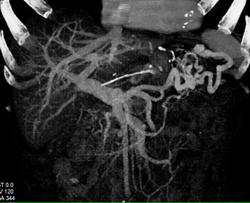

Gastro-jejunostomy